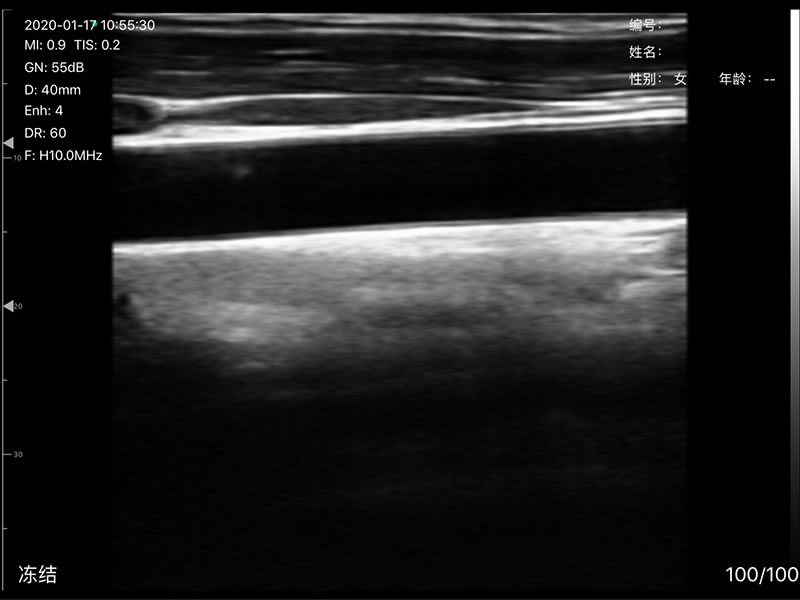

• 探头频率:相控阵2.2/3.6MHz,线阵7.5/10 MHz

• 扫描深度:相控阵90-190mm,线阵 20-100mm,可调

• 显示模式:B、B/M、Color、PW、PDI